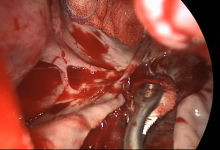

This video demonstrates decortication performed for a patient with multiple tension collections. The patient underwent a decortication process for multiple encysted collections that were causing tracheal deviation, airway compression, and severe shortness of breath. Initial radiologist reports showed pictures of multiple bullae, so an urgent lung volume reduction surgery was scheduled. When examining the chest cavity, it was found that the patient had multiple encysted empyemas and effusion.